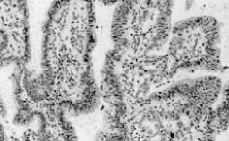

En nuestra unidad se realiza nueva citología que demostró la existencia de abundantes grupos celulares en forma de placas, mórulas o micropapilas, de bordes desflecados con gran densidad celular, superposición y ligero incremento de la relación núcleo/citoplasma (Fig. 1). Colposcópicamente se apreciaba la existencia de una gran zona de ectopia cervical con neoformación vegetante de 1,5 cm a las seis horarias, recubierta por tejido glandular con vasos atípicos, fácilmente sangrante (Fig. 2). Se realizó biopsia de dicha masa, observando una formación polipoide de 1,5 cm de diámetro de superficie micropapilar. El estudio microscópico revela un patrón predominantemente papilar ramificado, con pequeñas áreas de tipo velloso o de tipo glandular. El epitelio que tapiza estas estructuras está compuesto por células columnares no mucosas con estratificación, atipia leve y muy escasas mitosis. Los ejes conjuntivos de las papilas contienen células fusiformes de tipo fibroblástico e infiltrado crónico inespecífico (Fig. 3). Estos hallazgos son compatibles con el adenocarcinoma villoglandular bien diferenciado de cérvix.

Figura 3.Biopsia inicial.

Figura 4.Estudio microscópico de la biopsia inicial.

Macroscópicamente, este tumor se caracteriza por producir una lesión visible exofítica y friable que protuye desde el canal cervical. Microscópicamente se caracteriza por poseer un componente papilar en la superficie, generalmente formado por pequeñas papilas, y un componente velloso formado por glándulas ramificadas y alargadas separadas por estroma. En ningún caso de los publicados se encontró afectación del espacio vascular y linfático. A pesar de que los datos histopatológicos de este tumor son bastante definitorios, el diagnóstico diferencial debe incluir la cervicitis papilar en el contexto de una cervicitis crónica, el adenofibroma papilar de cérvix y el papiloma mulleriano(1).